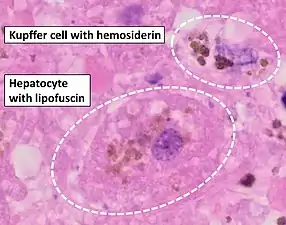

Stain for iron

Prussian blue is a common histopathology stain used by pathologists to detect the presence of iron in biopsy specimens, such as in bone marrow samples. The original stain formula, known historically (1867) as "Perls Prussian blue" after its inventor, German pathologist Max Perls (1843–1881), used separate solutions of potassium ferrocyanide and acid to stain tissue (these are now used combined, just before staining). Iron deposits in tissue then form the purple Prussian blue dye in place, and are visualized as blue or purple deposits.[39]

Histopathology of the liver, showing a Kupffer cells with significant hemosiderin deposition next to a hepatocyte with lipofuscin pigment. H&E stain.

Histopathology of the liver, showing a Kupffer cells with significant hemosiderin deposition next to a hepatocyte with lipofuscin pigment. H&E stain. Prussian blue staining, highlighting the hemosiderin pigment as blue.

Prussian blue staining, highlighting the hemosiderin pigment as blue. Prussian blue stain

Prussian blue stain